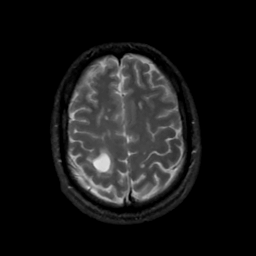

MR Study #8, March 31, 1991 -- Slice #39

[Home][Help][Clinical][Tour 1][Tour 2] Slice 39